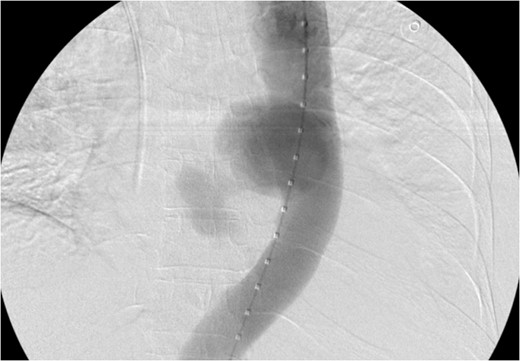

We report a case of a 71-year-old female of African American descent presenting with upper gastrointestinal bleeding found to have an aorto-esophageal fistula. Computed tomography scan was significant for a mid-thoracic pseudoaneurysm with active extravasation into esophagus. Sentinel bleeding in the esophageal lumen was also confirmed with esophagogastroduodenosopy (EGD). We present a case of successful endovascular treatment of a ruptured mycotic descending thoracic aorta that had fistulised into esophagus. TEVAR was performed using a Gore endoprosthesis stent graft without complication [4].

Aortogram showing successful deployment of covered stent graft.

TEVAR can be safely employed to treat an aorto-esophageal mycotic thoracic aneurysm when open repair is not possible because of patient’s comorbidity. Post-operatively our patient was asymptomatic and imaging demonstrated the stent graft in excellent position, without endoleak, and complete resolution of the aneurysm sac. Long-term follow-up is necessary for detection of endoleak, recurrence, or aneurysm propagation.